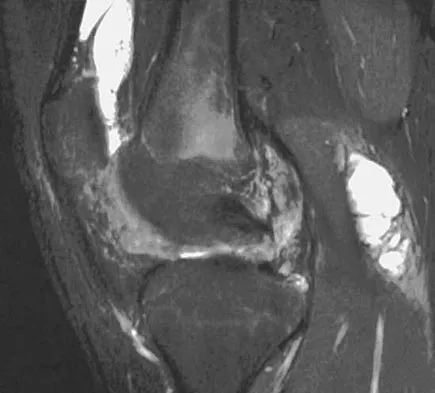

A 31-year-old woman has increasing pain and tightness in her right knee, with occasional stiffness and recurrent hemorrhagic effusions. MRI scans are shown in Figures 2a and 2b. What is the most likely diagnosis?

Explanation

PVNS is a rare inflammatory granulomatous condition of unknown etiology, and causes proliferation of the synovium of joints, tendon sheaths, or bursa. The disorder occurs most commonly in the third and fourth decades but can occur at any age. MRI provides excellent delineation of the synovial disease. Characteristic features of PVNS on MRI include the presence of intra-articular nodular masses of low signal intensity on T1- and T2-weighted images and proton density-weighted images. Synovial biopsy should be performed if there is any doubt of the diagnosis. Total synovectomy (open or arthroscopic) is required for the diffuse form, although recurrence is common. Rheumatoid arthritis and synovial chondromatosis are not typically associated with hemorrhagic effusions. De Ponti A, Sansone V, Malchere M: Result of arthroscopic treatment of pigmented villonodular synovitis of the knee. Arthroscopy 2003;19:602-607. Chin KR, Barr SJ, Winalski C, et al: Treatment of advanced primary and recurrent diffuse pigmented villonodular synovitis of the knee. J Bone Joint Surg Am 2002;84:2192-2202.